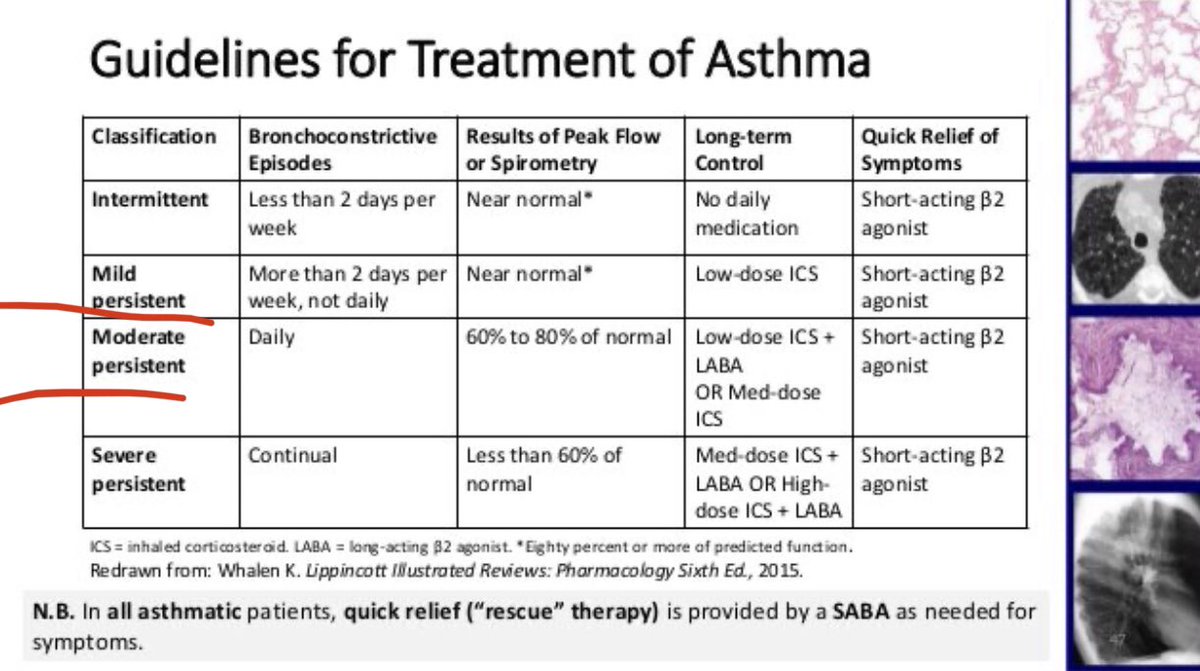

🔴خامسا :classfication of asthma ؟

#ملاحظه :

هذا السؤال مرره مهم عشان نكتب الخطه

التصنيف نعرفه بثلاث اشياء /

اولا: نشوف الاعراض

ثانيا: نشوف FEV الي هو/

Forced Expiratory Volume

وهو لازم يكون 95%

ثالثا : nighting awakening

وراح اشرحهم بالتفصيل تحت لا تخافو من الصورة 👇

First : #intermittent patient:

1- if symptom >2 days per week but not daily

2- FEV 1 80% , FEV / FVC > 80 %

ويكون النسبة اقل من 80%

3_nighting awakening: 3 or 4 times monthly

ويصحو بالشهر 3 او اربع مرات

اما الاطفال مرره او مرتين يصحوا من النوم بالشهر من تعب الربو

First : #Mild patient:

1- if symptom >2 days per week but not daily

2- FEV 1 80% , FEV / FVC > 80 %

3_nighting awakening:5 to 6 times per month

اما الاطفال 3 او 4 مرات يصحوا من النوم بالشهر

Second : #Moderate patient:

1- if Symptom Daily

2- FEV1 (60 - 80) % , FEV / FVC (75-80)%

يعني نشوف الFEV اذا من 60الى 80 هذا Moderate

3_nighting awakening: more than once weakly

اما الاطفال 4 الى 5مرات يصحوا من النوم

4_ #Sever patient:

المريض الشديد

1- if Symptom Throughout the day

2- FEV1 < 60 % predicted , FEV / FVC <75 %

اقل من 60% 😔

3-Nightly awakening: more than 5 times or daily

اما الاطفال اكثر من مره يصحوا من النوم بالاسبوع